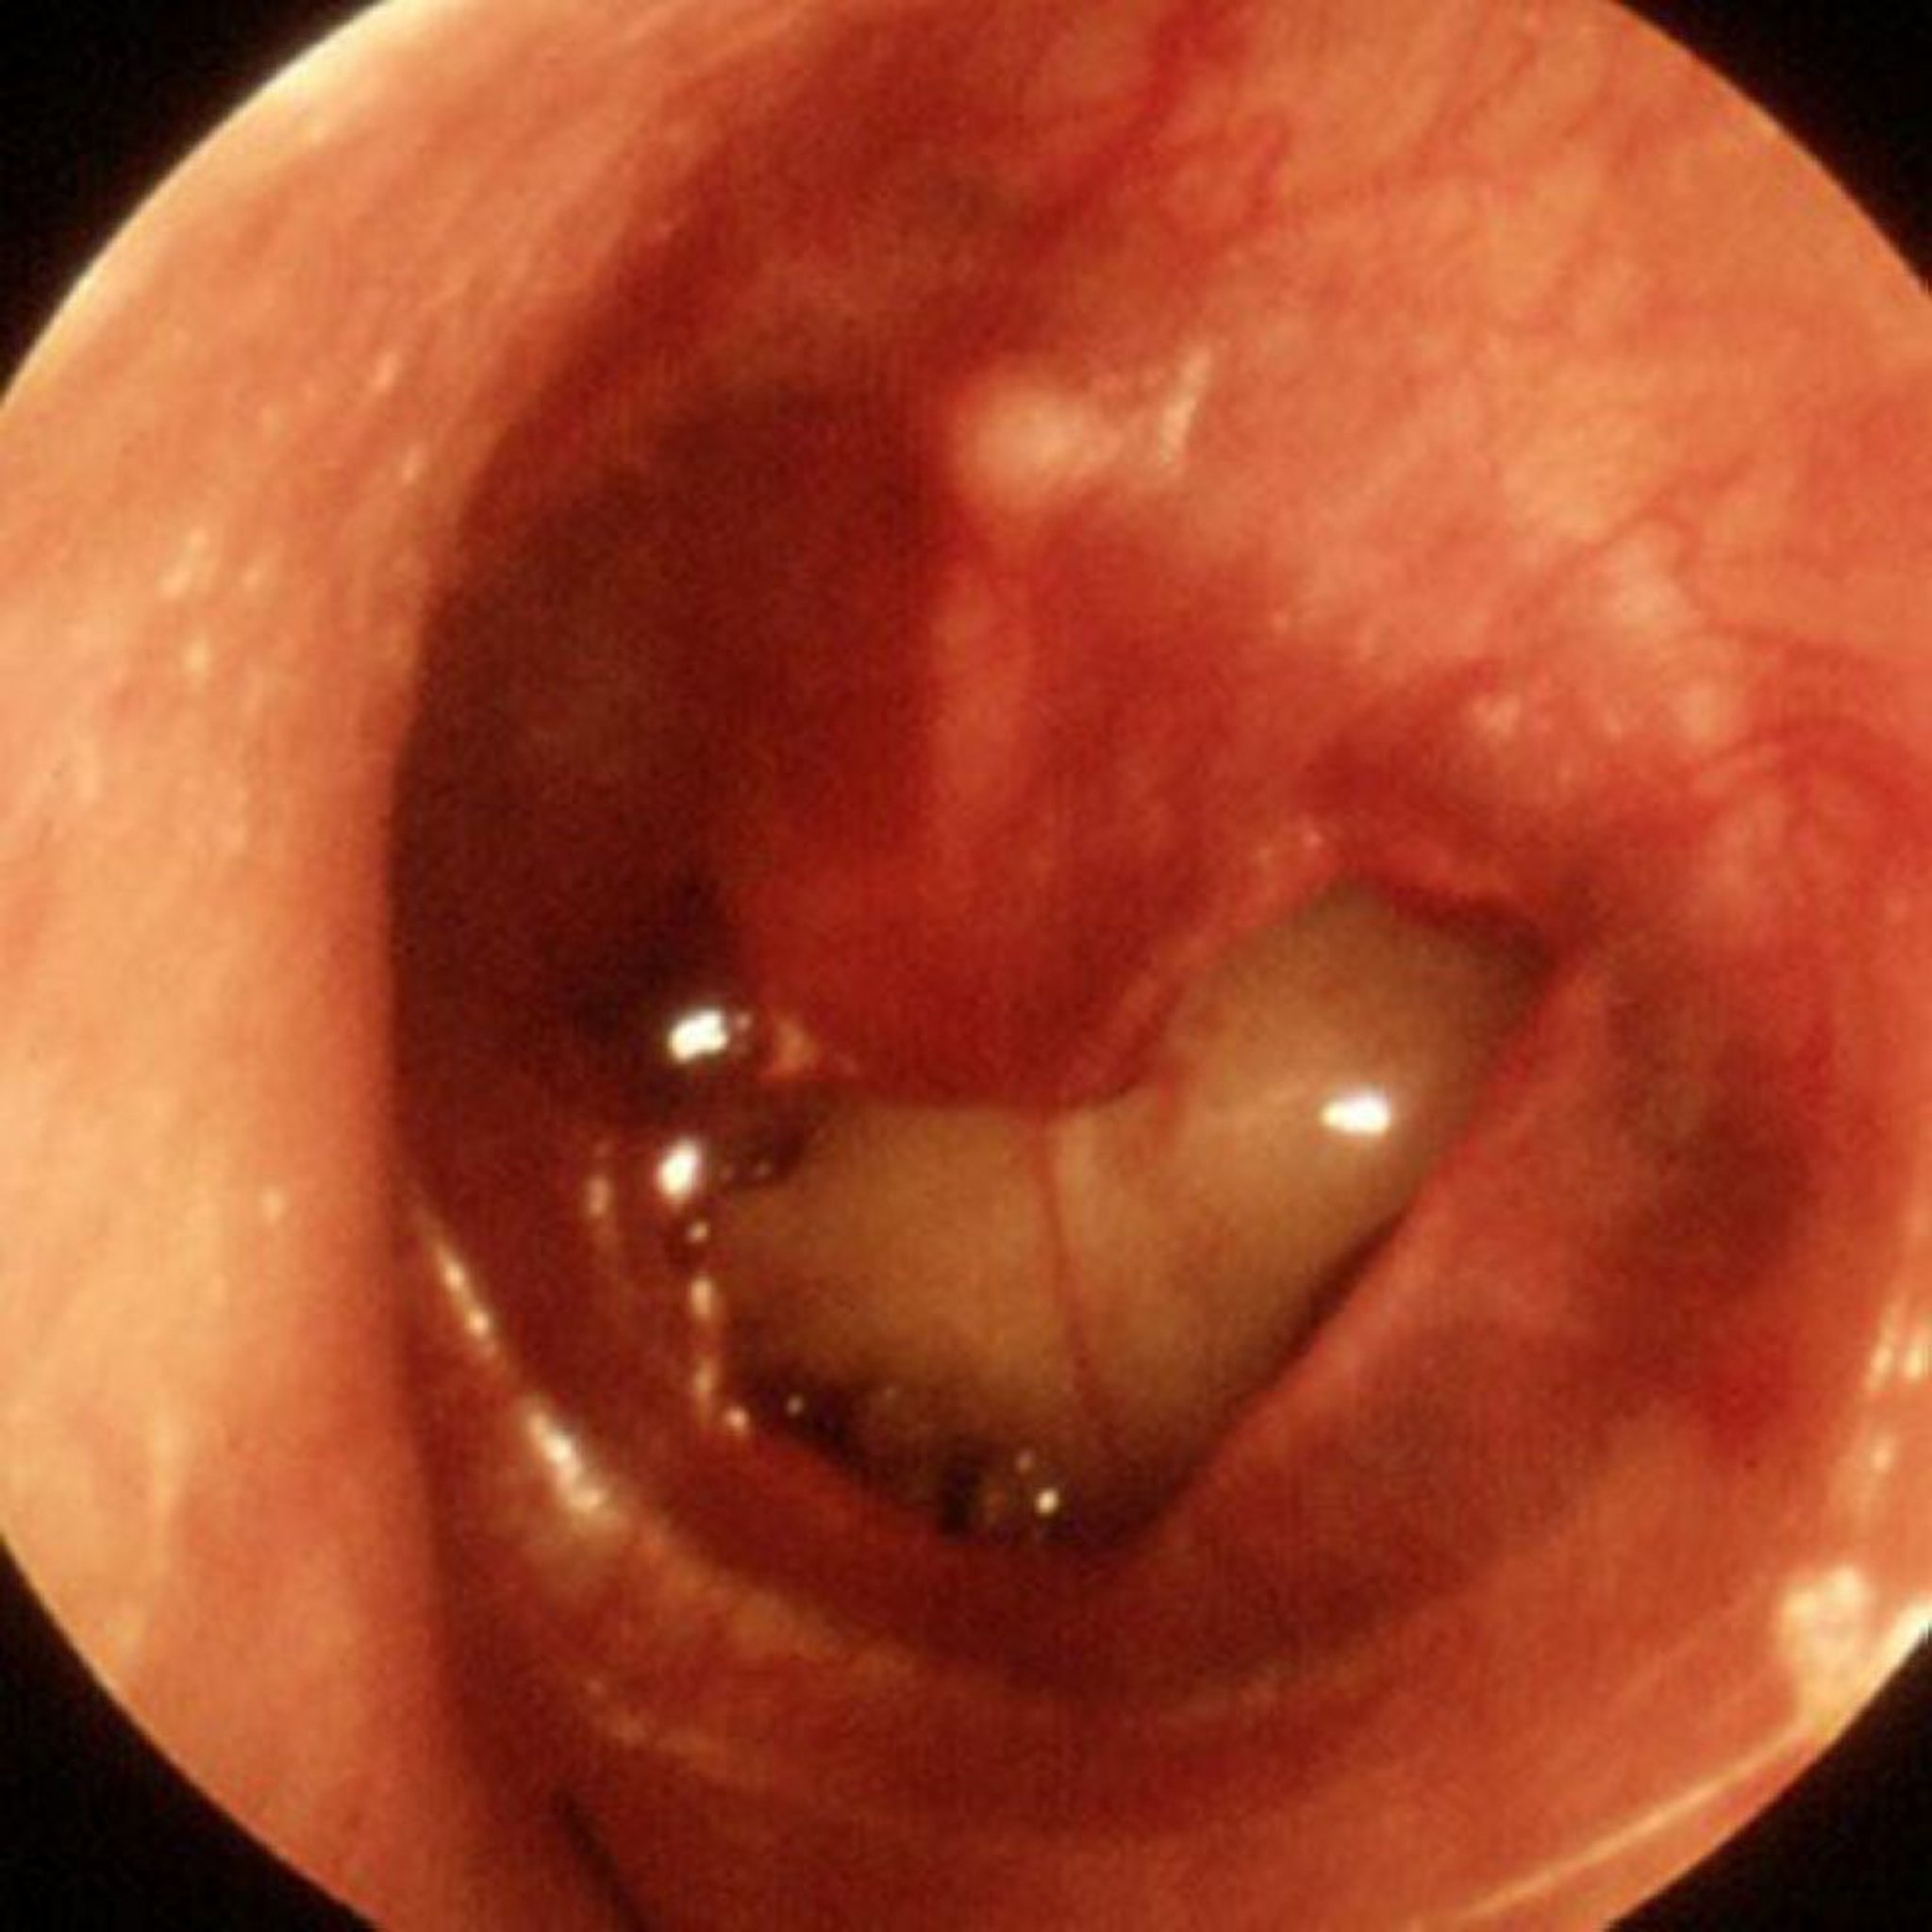

Perforación traumática de la membrana timpánica

En esta imagen se ve una perforación traumática grande.

Imagen proporcionada por Piet van Hasselt, MD.